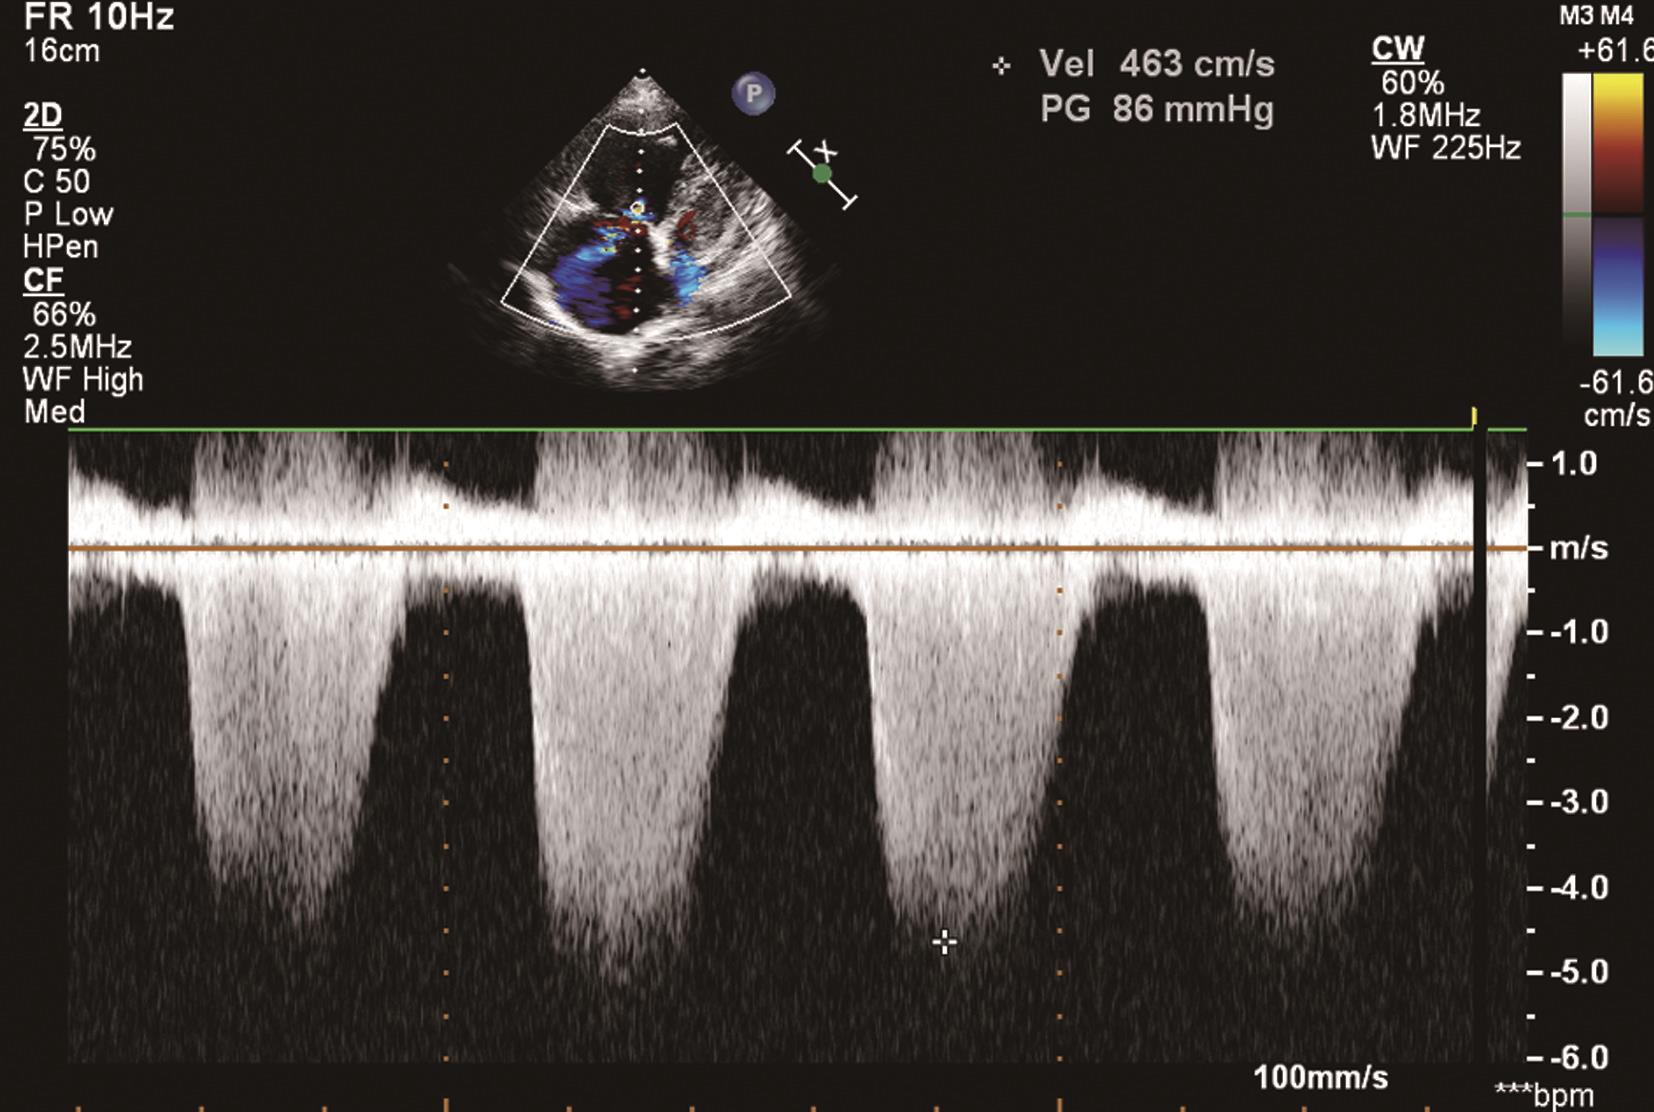

(1)心尖四腔心及大动脉短轴切面收缩期可探及花彩血流自右心室经三尖瓣反流入右心房,连续波多普勒可探及频谱呈收缩期位于基线下方的负向频谱(图6-2-2),并可测量反流的峰值流速以估测肺动脉收缩压。

图6-2-2 连续波多普勒显示三尖瓣频谱呈负向高速频谱